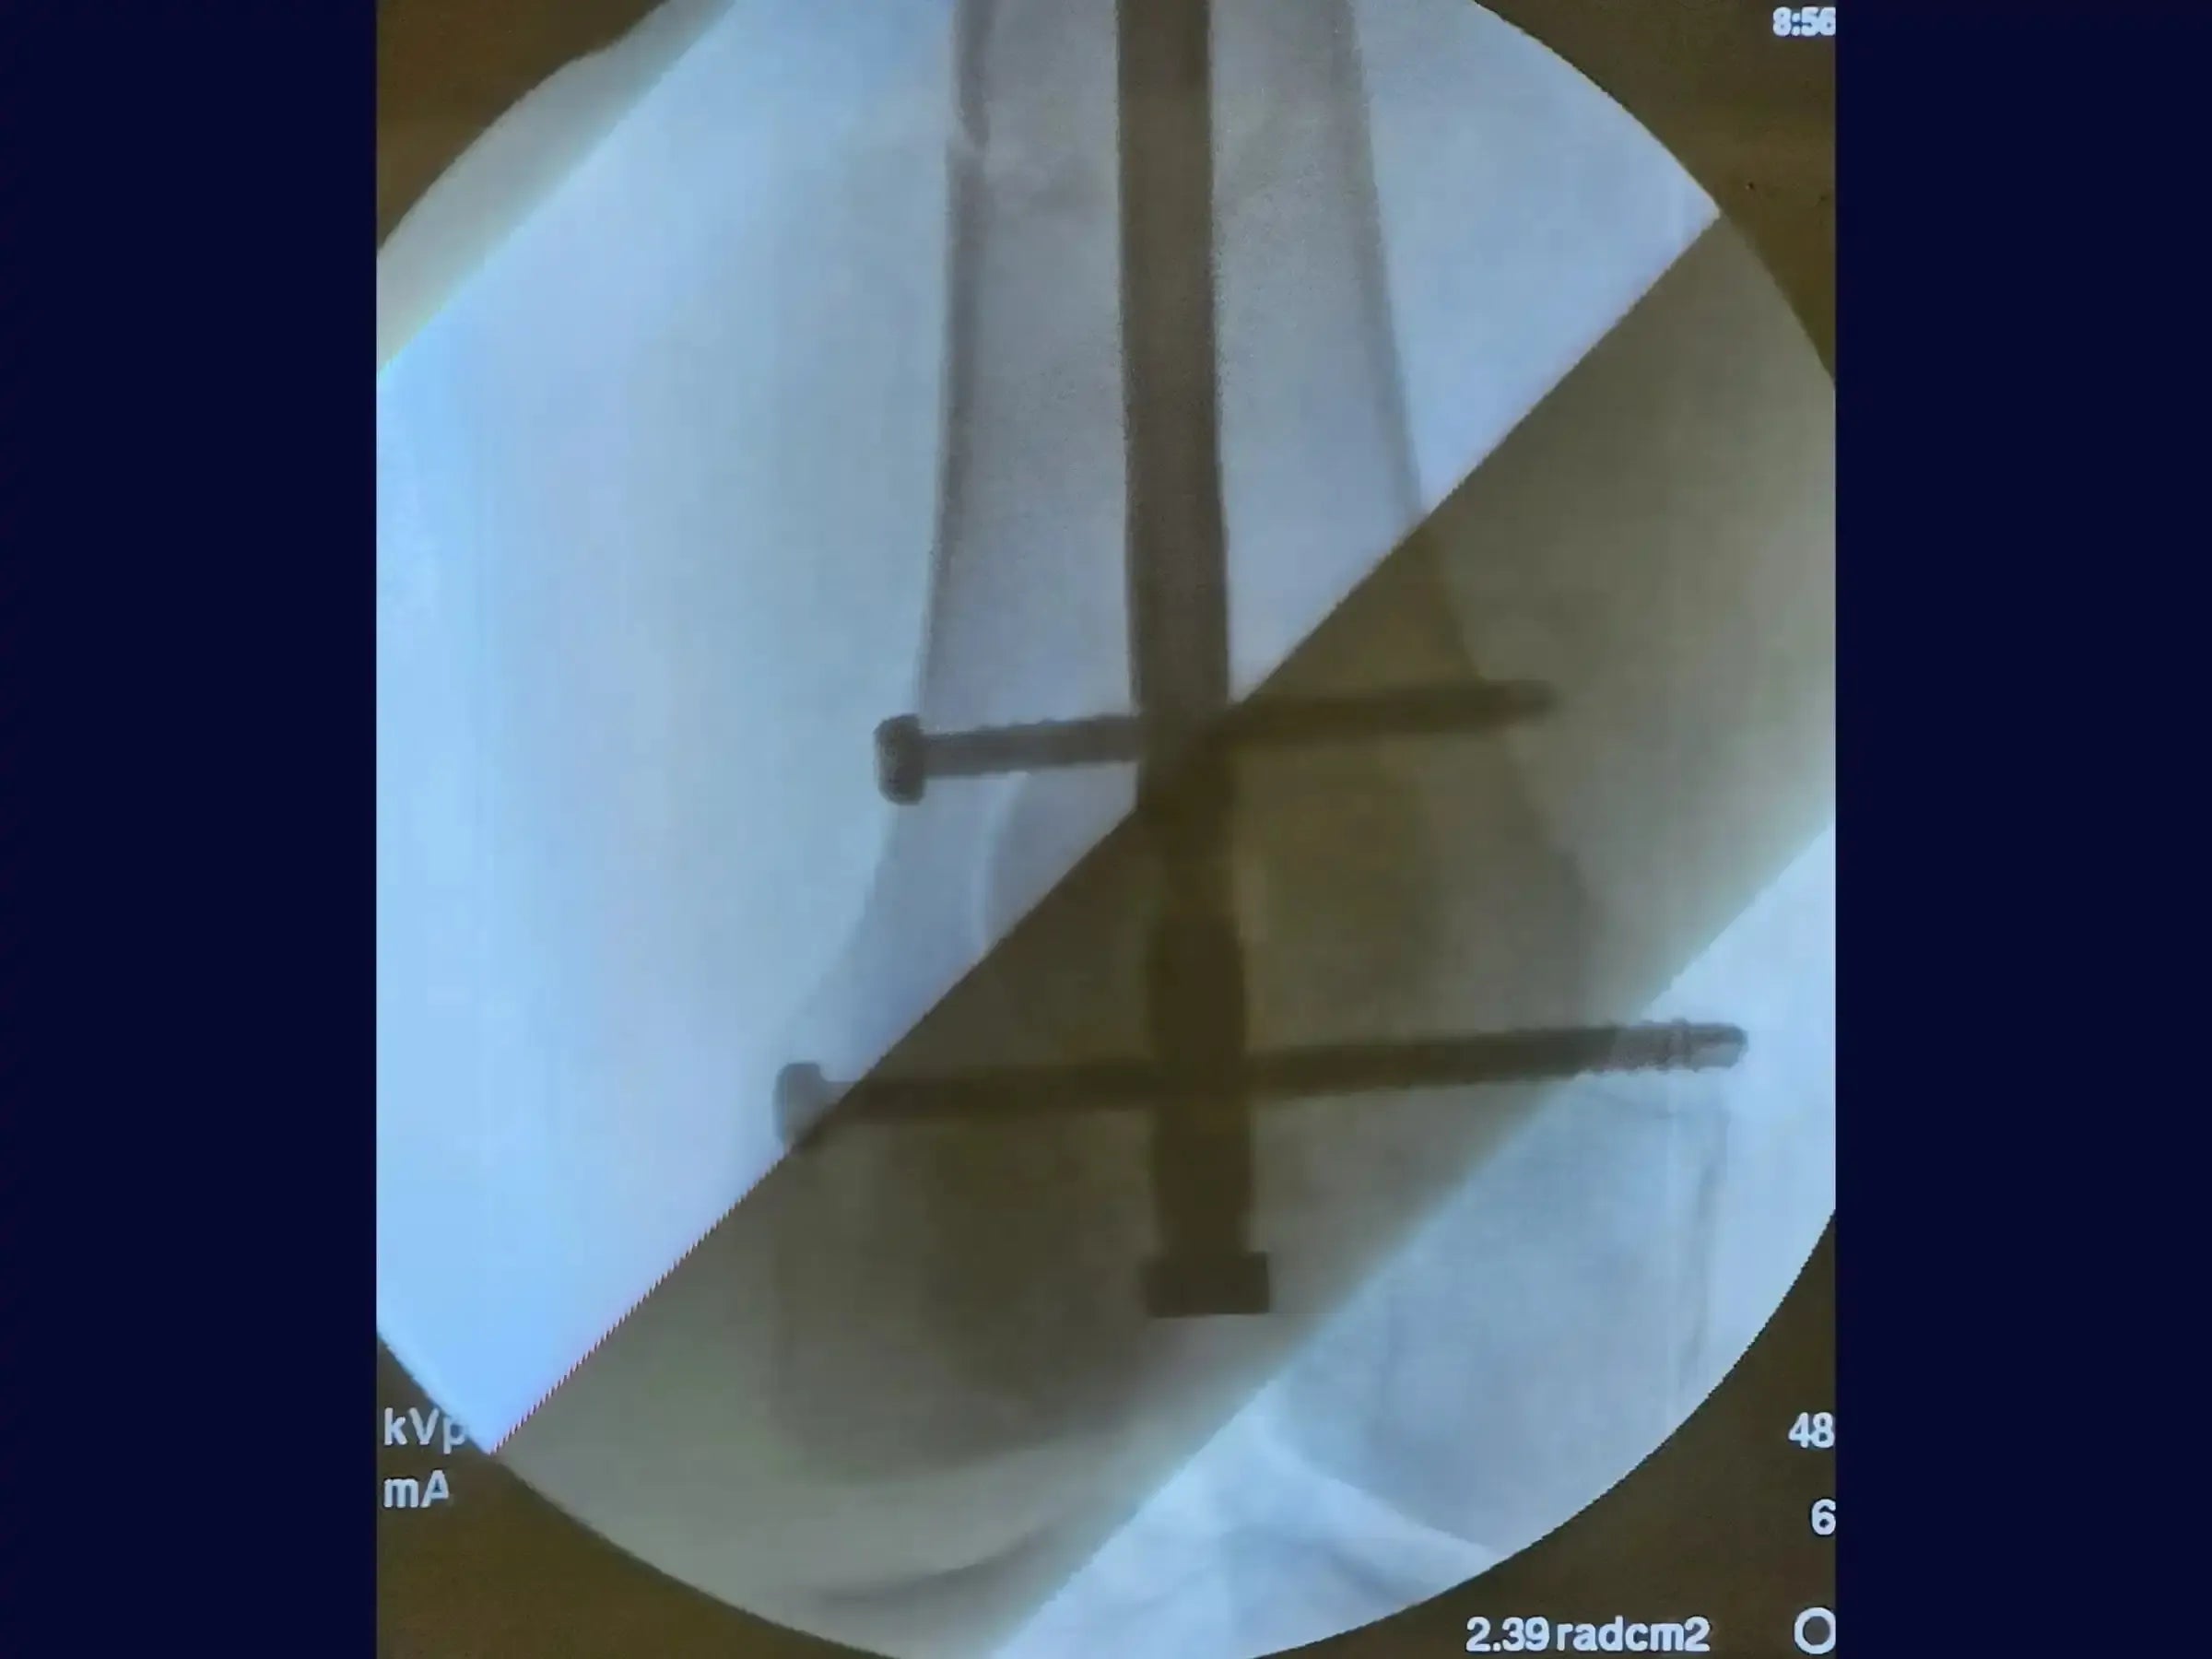

- Introdução da Haste Intramedular Retrógrada: Aprenda a introduzir a haste de forma retrógrada com conferência constante das imagens fluoroscópicas, garantindo que a extremidade da haste direcionada ao quadril ultrapasse o pequeno trocânter para evitar estresse e risco de fratura subtrocantérica.

- Bloqueio Distal Preciso: Domine a confecção dos parafusos de bloqueio distal utilizando guia específico, broca e medidor. Compreenda a necessidade de rotação interna do joelho para avaliar o tamanho correto do parafuso devido ao formato trapezoidal do fêmur distal, prevenindo falsas impressões.

- Bloqueio Proximal Minimamente Invasivo: Realize o bloqueio proximal sob fluoroscopia, com acesso minimamente invasivo, assegurando a conferência do perfil através da rotação da perna para certificar o tamanho correto do bloqueio, mesmo com grande massa muscular.

- Resultados Otimizados: Obtenha resultados cirúrgicos onde a haste está posicionada acima do pequeno trocânter e seguindo a linha de Blumensatt, sem proeminências no joelho, permitindo certa mobilidade no pós-operatório.